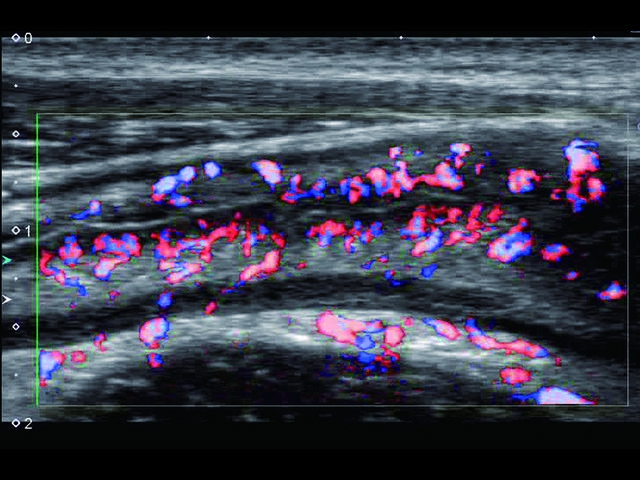

Обновленная версия легендарного УЗ-сканера. Стационарный аппарат экспертного класса Aplio 500 Toshiba NEW, визуализирует анатомические структуры в высоком разрешении. Модель позволяет выявить микрокальцификаты, новообразования, нарушения в работе сердца, сосудов и мышц. Присутствует функция виртуальной эндоскопии, 4D-сканирования, эластометрии тканей, УЗИ с контрастированием. За повышение качества изображения отвечают технологии ApliPure и Superb Microvascular Imaging. Первая задействует возможности пространственного и частотного кодирования, формирует цельный визуальный ряд с сохранением клинических маркеров. Вторая улучшает отображение микрососудистого русла, используя доплеровский эффект. Модель оснащена 21-дюймовым монитором, имеет 4 активных порта. Возможно подключение педиатрических, интраоперационных, лапароскопических и чреспищеводных датчиков.

• SMI. Опция, упрощающая визуализацию микроциркуляторного русла. С ее помощью обследуются сосуды с низкой интенсивностью кровотока, изучаются наиболее тонкие структуры. SMI упрощает диагностику новообразований, минимизирует вероятность ошибки.

Энергетический допплер:

Да

Высокочастотный импульсный допплер: